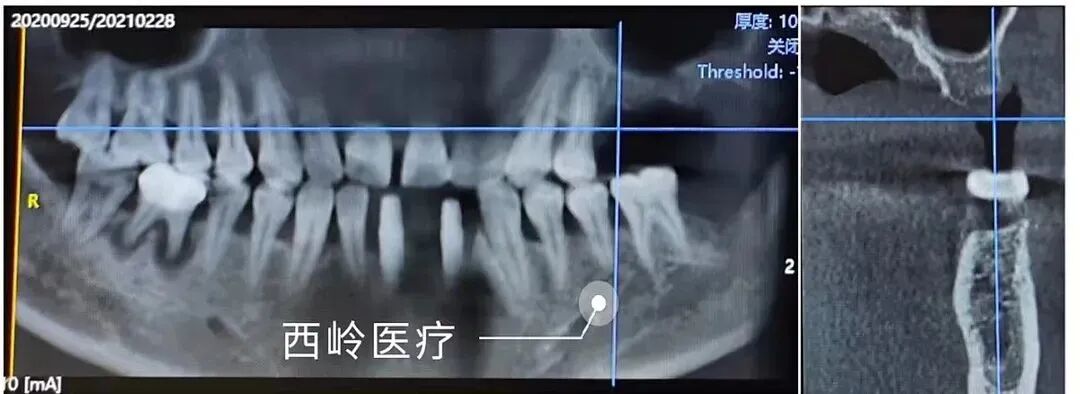

2021-2-28

#25#26#27 植骨后恢復狀況如下:牙槽嵴頂據(jù)上頜竇底壁高度4-6毫米。